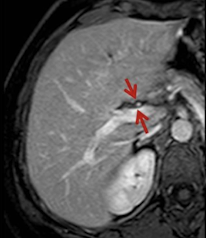

What is this and what type of scan

Liver Cirrhosis, US